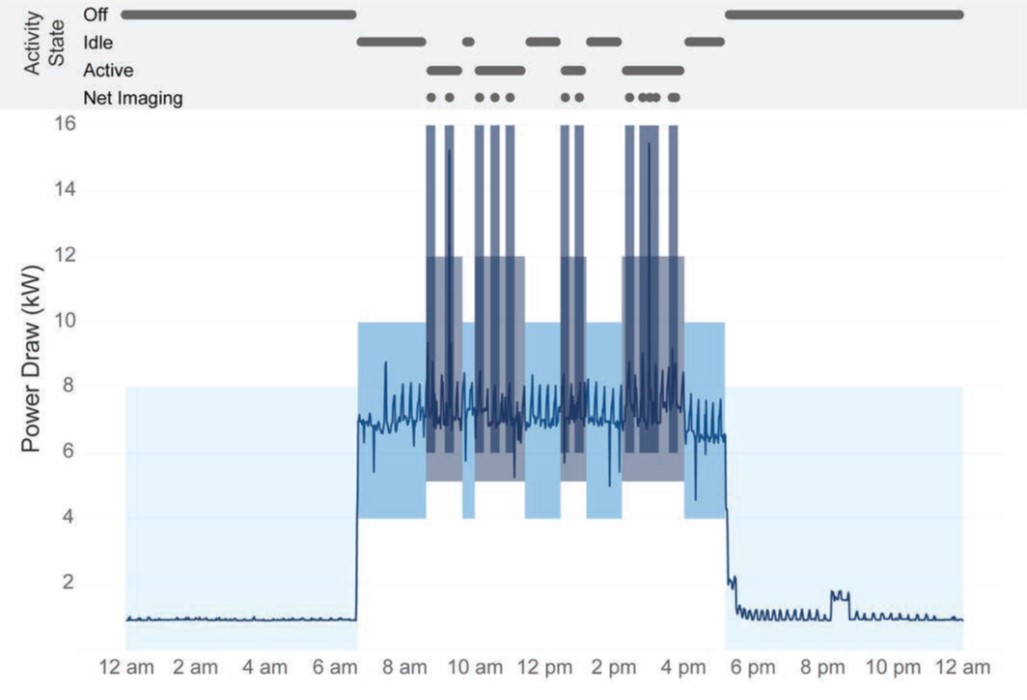

“Strategic operational adjustments (e.g., powering down idle systems) can substantially decrease interventional imaging systems’ carbon emissions and electricity costs.” Learn more ➡️ bit.ly/3VxNlrv Jan Vosshenrich, MD UniSpitalBaselCH AJR #RadNews #IRad #RadAdmin

The following tweetorial comes from Jan Vosshenrich, MD (Jan Vosshenrich, MD) lead author of the recently published AJR article “Interventional Imaging Systems in Radiology, Cardiology, and Urology: Energy Consumption, Carbon Emissions, and Electricity Costs”